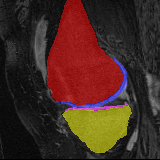

Moving Target Mono-0 Mono-5 DA-1 DA-5 Mono-200 Refer to caption Refer to caption Refer to caption Refer to caption Refer to caption Refer to caption Refer to caption Refer to caption Refer to caption Refer to caption Refer to caption Refer to caption Refer to caption Refer to caption

Image Manual Seg DA-1 Mono-21 DA-21 Mono-65 Refer to caption Refer to caption Refer to caption Refer to caption Refer to caption Refer to caption

Figure 2:  Examples of knee MRI registration (top) and brain MRI segmentation (bottom) results. Top: The first two columns are the moving image/segmentation and the target image/segmentation followed by the warped moving images (with deformation grids)/segmentations by different models. Bottom left to right: original image, manual segmentation, and predictions of various models. Mono-i𝑖i and DA-i𝑖i represent the mono- and DA models with i𝑖i manual segmentations respectively.

Results: All trained networks are evaluated using Dice overlap scores between predictions and the manual segmentations for the segmentation network, or between the warped moving segmentations and the target segmentations for the registration network. Tabs. 1 and 2 show results for the knee and brain MRI experiments respectively in Dice scores (%). Fig. 2 shows examples of knee MRI registrations and brain MRI segmentations.

Qualitative results: DA achieves more anatomically consistent registrations than the mono-networks on the knee (Fig. 2) and Brain MRI samples (see supplementary material).

Moving Target Mono-0 Mono-21 DA-1 DA-21 Mono-65 Refer to caption Refer to caption Refer to caption Refer to caption Refer to caption Refer to caption Refer to caption Refer to caption Refer to caption Refer to caption Refer to caption Refer to caption Refer to caption Refer to caption

Image Manual Seg DA-1 Mono-5 DA-5 Mono-200 Refer to caption Refer to caption Refer to caption Refer to caption Refer to caption Refer to caption

Figure 4: Examples of brain MRI registration (top) and knee MRI segmentation (bottom) results. Top: The first two columns are the moving image/segmentation and the target image/segmentation followed by the warped moving images/segmentations by different models. Bottom left to right: original image, manual segmentation, and predictions of various models. Mono-i𝑖i and DA-i𝑖i represent the mono- and DA models trained with i𝑖i manual segmentations respectively.